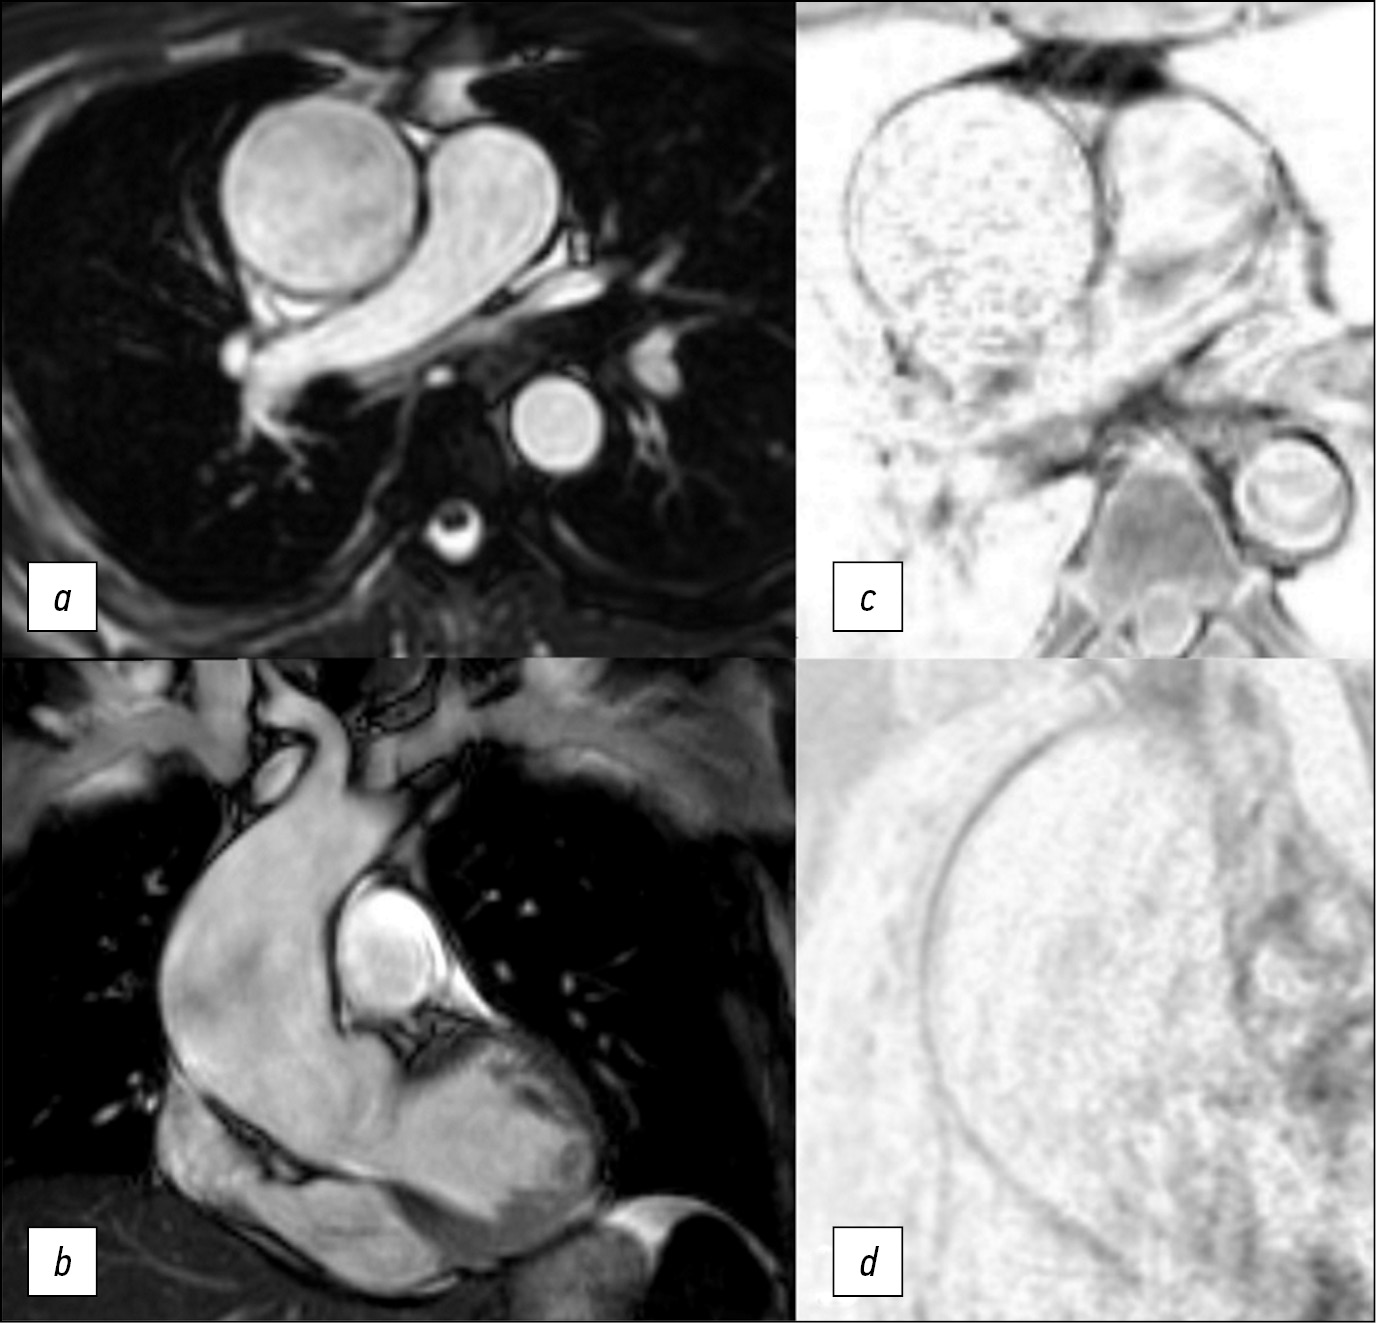

患者接受了与心电图同步的主动脉MRI和心脏MRI。该检查是在带有专门线圈的1.5Т磁共振成像上进行的。使用没有对比增强的T2和T1加权图像,再使用增强的T1加权图像。在MRI扫描期间进行了对比增强的血管造影(图1)。升主动脉最大直径5.4 cm,动脉瘤近端和尾部之间的距离为9 cm;头臂干口前的主动脉直径——3.4 cm,左颈总动脉和锁骨下动脉口之间——2.4 cm,下降部分——2.3 cm。头臂干边缘到动脉瘤颅缘的距离为5.5 cm。

为了评估主动脉壁的弹性和收缩性,使用了在轴向和冠状投影中以稳态自由进动(steady-state free precession, SSFP)模式获得的原生图像(见图1)。

图1。在轴位(a)和冠位(b)中以SSFP模式获得的图像,在轴位(c)中以T1-SE(主动脉瘤的中间三分之一) ,在斜投影中以“黑血”模式获得的T1-SPIR(d)。主动脉壁变薄,中部更明显。

在SSFP模式下,我们能够清楚地显示出心动周期期间主动脉壁的运动和血流方向。在QFlow序列(包括导管的可视化)中进行MRI以定量估值脉搏波速度,或如需评估瓣膜的功能。升主动脉壁的厚度和血管化是通过轴位的T1加权自旋回波(T1-spin echo, T1-SE)和梯度回波(T1-gradient-echo, GRE)序列中取得照片评估的,具有光谱选择性信号抑制的T1加权序列,在“黑血”模式(图2)中的光谱饱和和反转恢复序列(Т1-spectral presaturation with inversion recovery, T1-SPIR),在T2-在轴向和倾斜投影的“黑血”模式中具有光谱抑制的加权序列。

MRI数据显示,患者升主动脉从根部扩张 至9 cm长,最大直径为5.5 cm。动脉瘤定位区域的主动脉壁均匀变细,中部更为明显,搏动减弱,有运动障碍迹象,从动脉瘤囊边缘到头臂干主动脉壁完整不超过3 cm(见图2),主动脉直径在此水平不超过3.5 cm。还应该注意患者的二瓣叶型主动脉瓣。

图2。对比增强磁共振血管造影,动脉期,屏气,斜投影,主动脉3D重建(a); 在升主动脉瘤远端边缘的“黑血”模式下轴位的T1-SPIR(b);在斜投影中的头臂干口的前面(c)。完整的主动脉壁(箭头),手术治疗后胸主动脉的计算机断层扫描血管造影(d)。

手术治疗后,患者接受了胸主动脉CT血管造 影(见图2)。术后图像显示,对比主动脉腔的直径没有扩张,也没有内漏的现象。